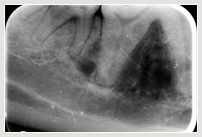

Die Diagnostik umfasst Anamnese und Klinik, wobei die Mundhöhle komplett inspiziert und Umfangsvermehrungen und Asymmetrien gegebenenfalls palpiert werden sollten. Die Röntgendarstellung dient der genaueren Erfassung der Ausdehnung des Tumors. Die Therapie aggressiver oraler Tumoren geschieht im Idealfall in Absprache aller Beteiligten, also dem Tierarzt, Onkologen, Bestrahlungstherapeuten und dem Besitzer. Wobei die frühzeitige chirurgische Entfernung relativ kleiner Tumoren optimal ist. Bei der Behandlung von oralen Tumoren kann auch bei Tieren zu sehr befriedigenden Ergebnissen führen, dennoch ist ist aber vor allem viel Überzeugungsarbeit der Besitzer notwendig.

Tumor im Unterkiefer Zahnröntgen im Tumorbereich Entfernter Kieferteil unter Tumor